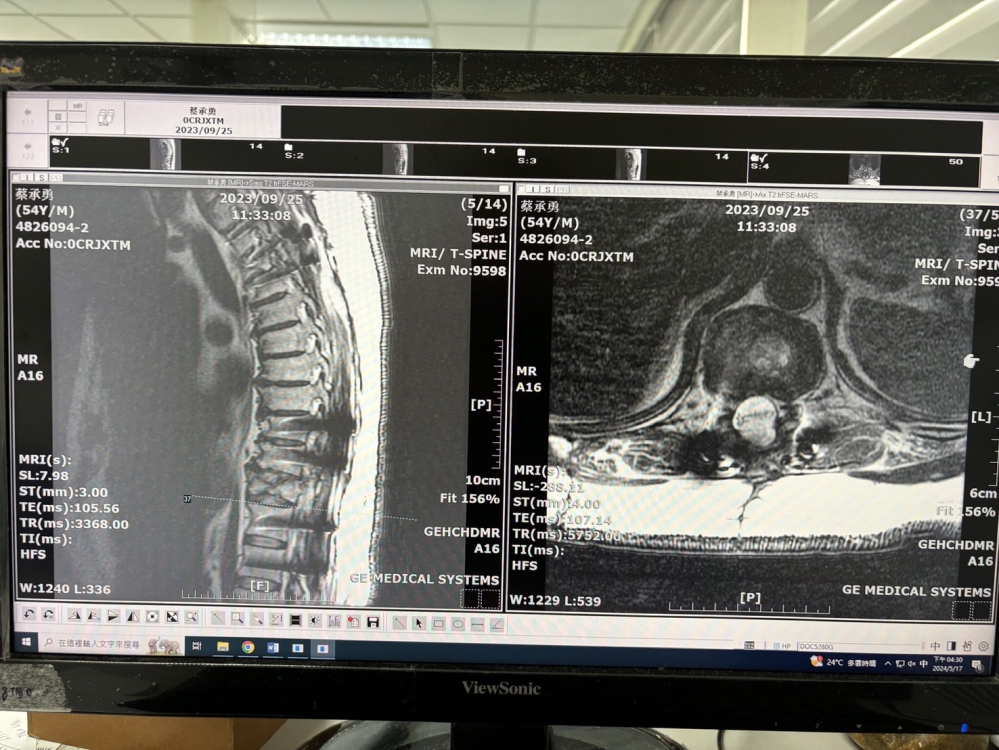

50歲的蔡先生努力扶著欄杆行走,對他來說,每一步雖然走的艱辛卻得來不易。2022年的他,因為跌落的意外導致脊髓損傷嚴重,原本被醫師宣告不能再行走,如今的他卻能夠站起來。蔡先生說,首次做完自動燒,從經過1年之後,大腿開始感覺有力量,然後腳趾頭也會動。

鄭宏志醫師表示,過去在大白鼠上的試驗上,結果它就是一個全部斷,然後它要重新找,然後有功能復原的狀況就是證實中樞神經是可以再生的。自1996年發表研究後,推翻了數百年來神經無法再生的理論為全世界及則損傷患者帶來希望,28年來也成功讓三名患者的神經得以修復。